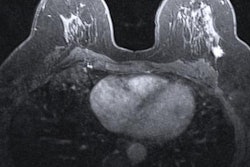

Dense breast tissue is considered a risk factor for breast cancer because it can reduce mammography's sensitivity by masking cancer lesions. It is typically evaluated using the four-point BI-RADS scale, noted a group led by Dr. Veronica Magni of the Università degli Studi di Milano. Women with dense tissue are typically referred for supplemental breast cancer screening via ultrasound or breast MRI.